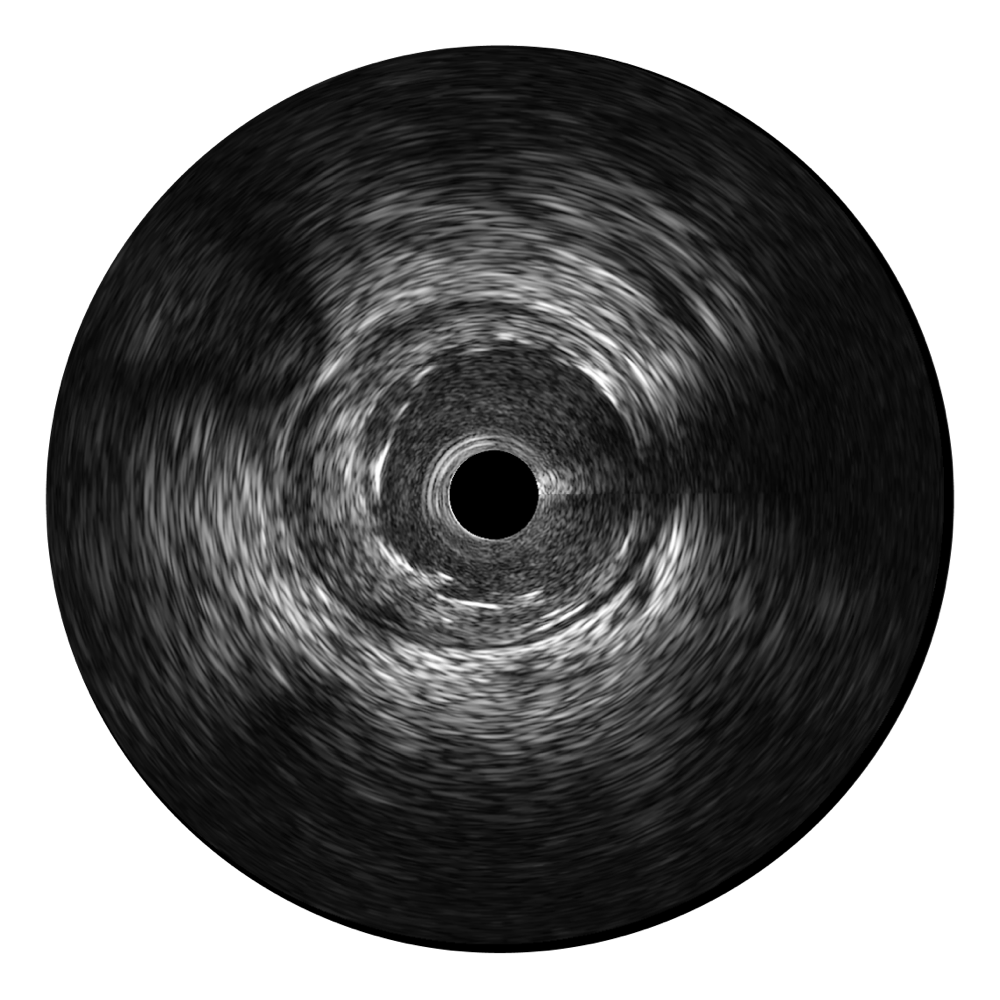

新葡的京集团8814检测站宽频IVUS图像

传统IVUS图像

对比传统IVUS导管成像,新葡的京集团8814检测站宽频IVUS图像的近场支架梁显影更细腻,远场中膜外血管仍清晰可辨,兼顾远中近,兼顾分辨力与穿透深度